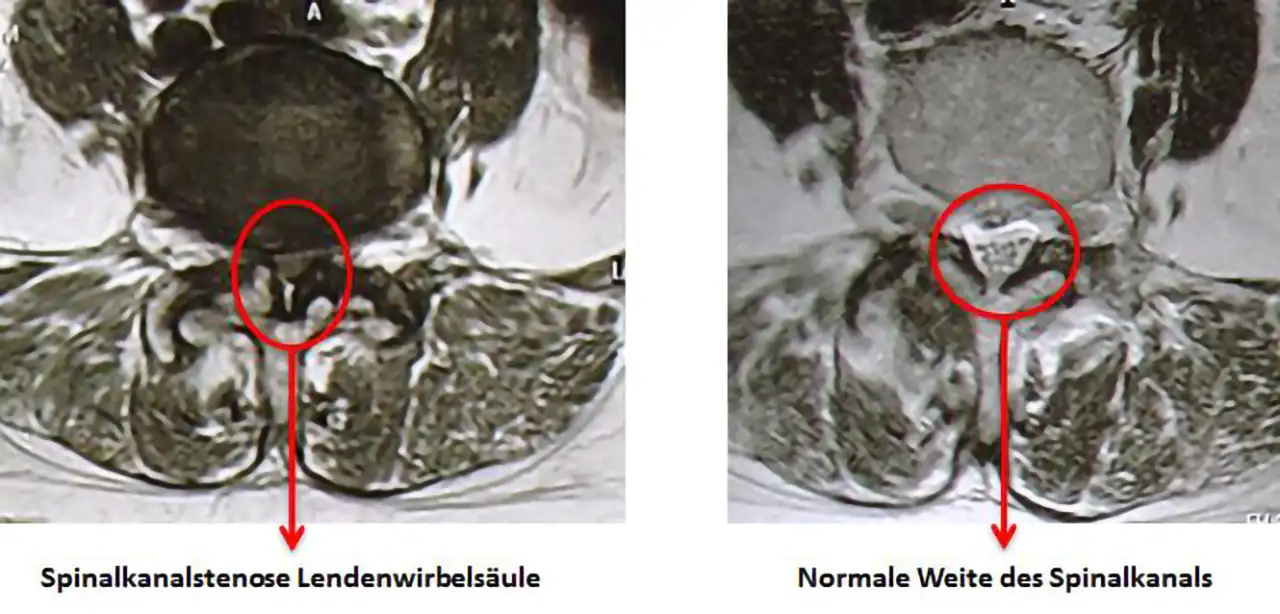

Die Spinalkanalstenose ist eine Verengung des Rückenmarkkanals (Spinalkanals). Über 90 Prozent der Spinalkanalstenosen oder eben Verengungen des Rückenmarkkanals sind abnützungsbedingt. Die Spinalkanalstenose kann in allen Wirbelsäulenabschnitten vorkommen; sie tritt aber am Häufigsten in den Gegenden der grössten Beanspruchungen auf, also im Bereiche der mittleren bis unteren Lendenwirbelsäule sowie in der mittleren Halswirbelsäule (cervikale Spinalkanalstenose, lumbale Spinalkanalstenose).

Die Diagnose der Spinalkanalstenose sowohl im Bereiche der Halswirbelsäule als auch im Bereiche der Lendenwirbelsäule wird mittels Anamnese, klinischer und neurologischer Untersuchung gestellt. Zur Verifikation der Verdachtsdiagnose kann ein MRI durchgeführt werden, oder allenfalls auch eine Myelogrphie.